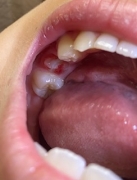

昨日最後の乳歯が抜けて、隣接していた6歳臼歯の近心側の歯茎のきわ辺りに白濁と一部分にごく小さく薄茶色の様な箇所がありました。

(目視では欠損などがあるかは分からず)。

写真を拝見した限りエナメル質に限定した軽い脱灰と着色のように見えます、それほど深刻ではないように思います、お菓子に気を付けてフロスを使う事で再石灰化すると思います。